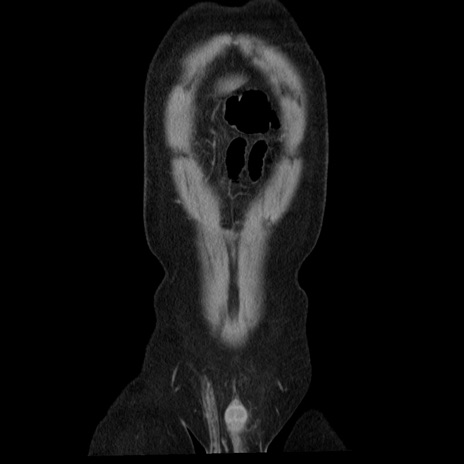

横断像

【症例】40歳代男性

【現病歴】2日前から胃痛あり。徐々に周期的な激痛に変化した。本日になっても激痛があるため受診。

【身体所見】意識清明、BT 38-39℃台あり、腹部:膨満、やや硬、右下腹部に圧痛あり。

【データ】WBC 8500、CRP 23.26